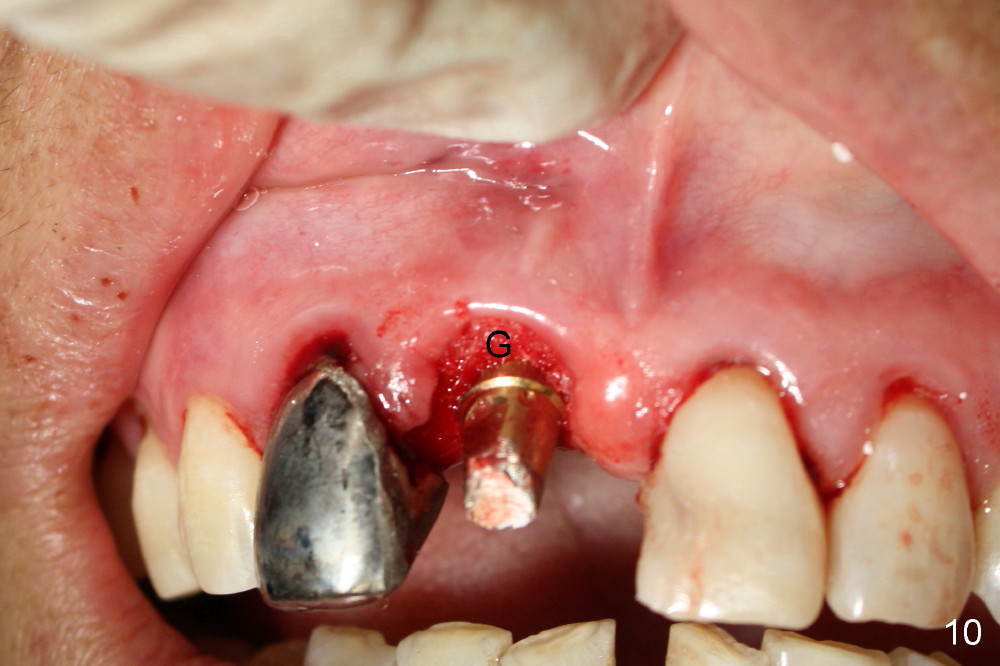

A 64-year-old lady requests replacing #7 and 8 crowns (Fig.1,2). When #8 is extracted, the labial plate is found to be missing (Fig.3). Following 2 mm pilot drill (Fig.4,5 P), 3.8 mm tap drill (Fig.6,7 T) and 4.5x14 mm implant (Fig.8 I) and 4.8 mm abutment (Fig.9 A), corticocancellous bone is harvested from the left tuberosity and placed in the labial gap of the socket (Fig.10 G). Collagen dressing is placed over the bone graft (Fig.11 C). The former is secured in place by an immediate provisional (P).